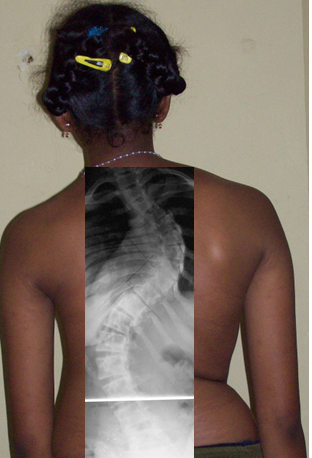

Case 1: Adolescent Idiopathic Scoliosis

Patient: Chaitra Age: 14Y/F

Condition: Severe adolescent idiopathic scoliosis (100° curvature)

Chaitra’s parents were concerned about her worsening spinal curvature, however couldn’t afford the high surgery costs quoted elsewhere. When they approached Dr. Yogesh K. Pithwa, he developed a cost-effective surgical plan using minimal pedicle screws and sublaminar wires — an innovative approach that maintained surgical precision while reducing implant cost.

The surgery successfully corrected her spinal deformity, restored balance and posture. This case proved that the best spine surgery in Bangalore doesn’t have to be the most expensive — it just needs the right expertise and compassionate thinking.